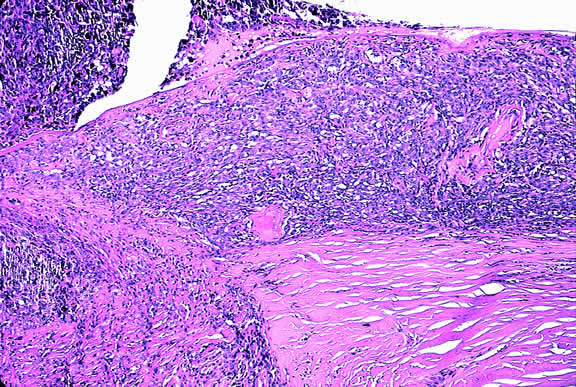

The ready visibility of many iris melanomas leads to their diagnosis at an earlier age and a smaller size (Fig. 10). Iris melanoma typically is discovered when a patient or his or her physician detects a focal pigmented blemish. Higher grade iris melanomas, or ciliary body tumors that invade the anterior chamber, can seed the iris and anterior chamber causing acquired hyperchromic heterochromia iridum (Fig. 11). Secondary glaucoma often accompanies the change in iris color. Not infrequently, the underlying diagnosis may be overlooked and the patient is treated for glaucoma, especially when a melanoma is nonpigmented or confined to the periphery of the iris or the trabecular meshwork.

Fig. 11. Patient with iris heterochromia caused by diffuse iris melanoma.

Iris melanoma is relatively rare, constituting between 4% to 15% of uveal melanomas in various series.93 The studies with higher reported incidences may reflect inclusion of nevi. Iris melanomas differ in some respects from tumors of the posterior segment. Most are low-grade spindle cell tumors (Fig. 43). However, iris melanomas with epithelioid cells occasionally are encountered (Fig. 44). Many pigmented iris tumors actually are nevi,94 and relatively few of these enlarge when observed. Several studies have shown that the risk of enlargement in 5 years is only 5% to 6% after a subset of promptly treated lesions is excluded.95,96 One study showed that iris tumors are likely to be considered melanomas and be treated promptly if the basal diameter is greater than 3 mm, pigment dispersion or prominent tumor vascularity are present, the intraocular pressure is elevated, or there are tumor-related symptoms.95 The mean age of patients with iris melanomas is about 10 years younger (age 43 years) than the age of patients with posterior segment melanomas.97 The prognosis of iris melanoma is also relatively favorable compared with tumors of the posterior segment. Shields and coworkers97 studied 169 patients with histologically confirmed iris melanoma and found that distant metastases developed in 5% at 10-years follow-up. The relatively small size of most iris melanomas probably is a major factor in their good prognosis. The prognosis of iris melanomas actually may be similar to posterior segment tumors of similar size and cell type. Diffuse iris melanomas that cause heterochromia iridis and secondary glaucoma are a rare but clinically important group of iris tumors.98,99 Many diffuse iris melanomas are higher grade tumors that contain epithelioid cells, which are poorly cohesive and prone to aqueous dispersal. Glaucoma surgery should be avoided in such cases. It invariably fails and puts patients at greater risk for extraocular extension and metastasis.100